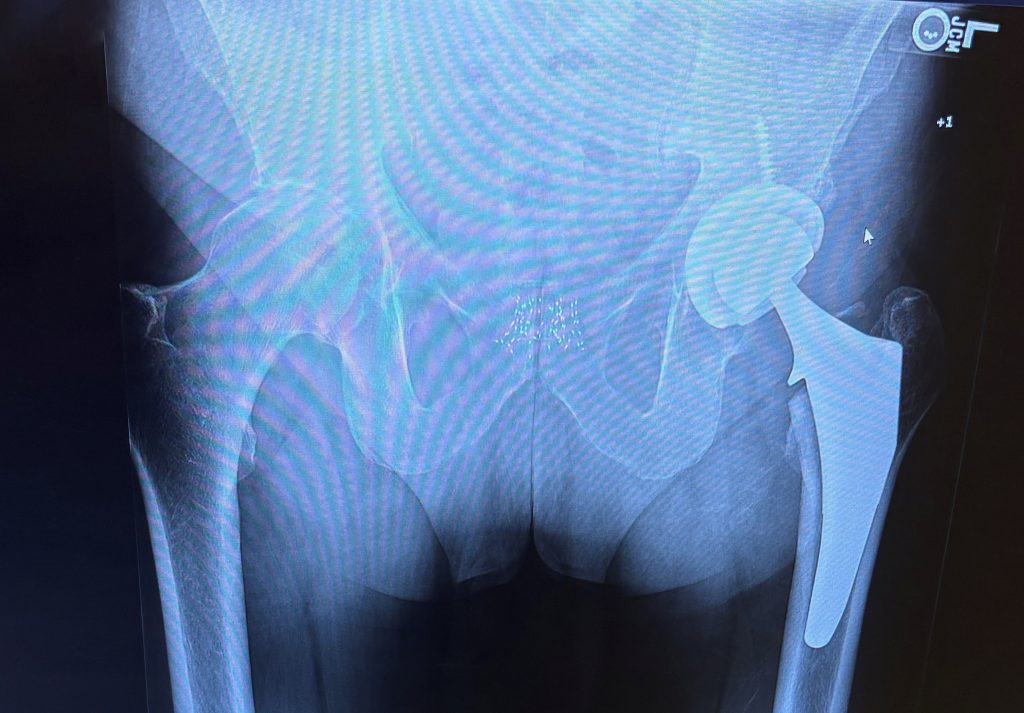

Hip Replacement

I went home the day of the surgery and walked up the steps to my room. I had a tough time sleeping the first couple of nights, but I was off medications in two days and slowly walking around the house with no issues right away. After a week, aside from needing a lot of ice, I felt reborn. I was and am a little surprised by the knee and ankle swelling but the surgery was a little over five weeks ago and I'm walking up to two miles a day and extremely pleased. All the OR nurses told me Dr. McLawhorn is the best surgeon in the country and I completely believe it. Great people and great results.